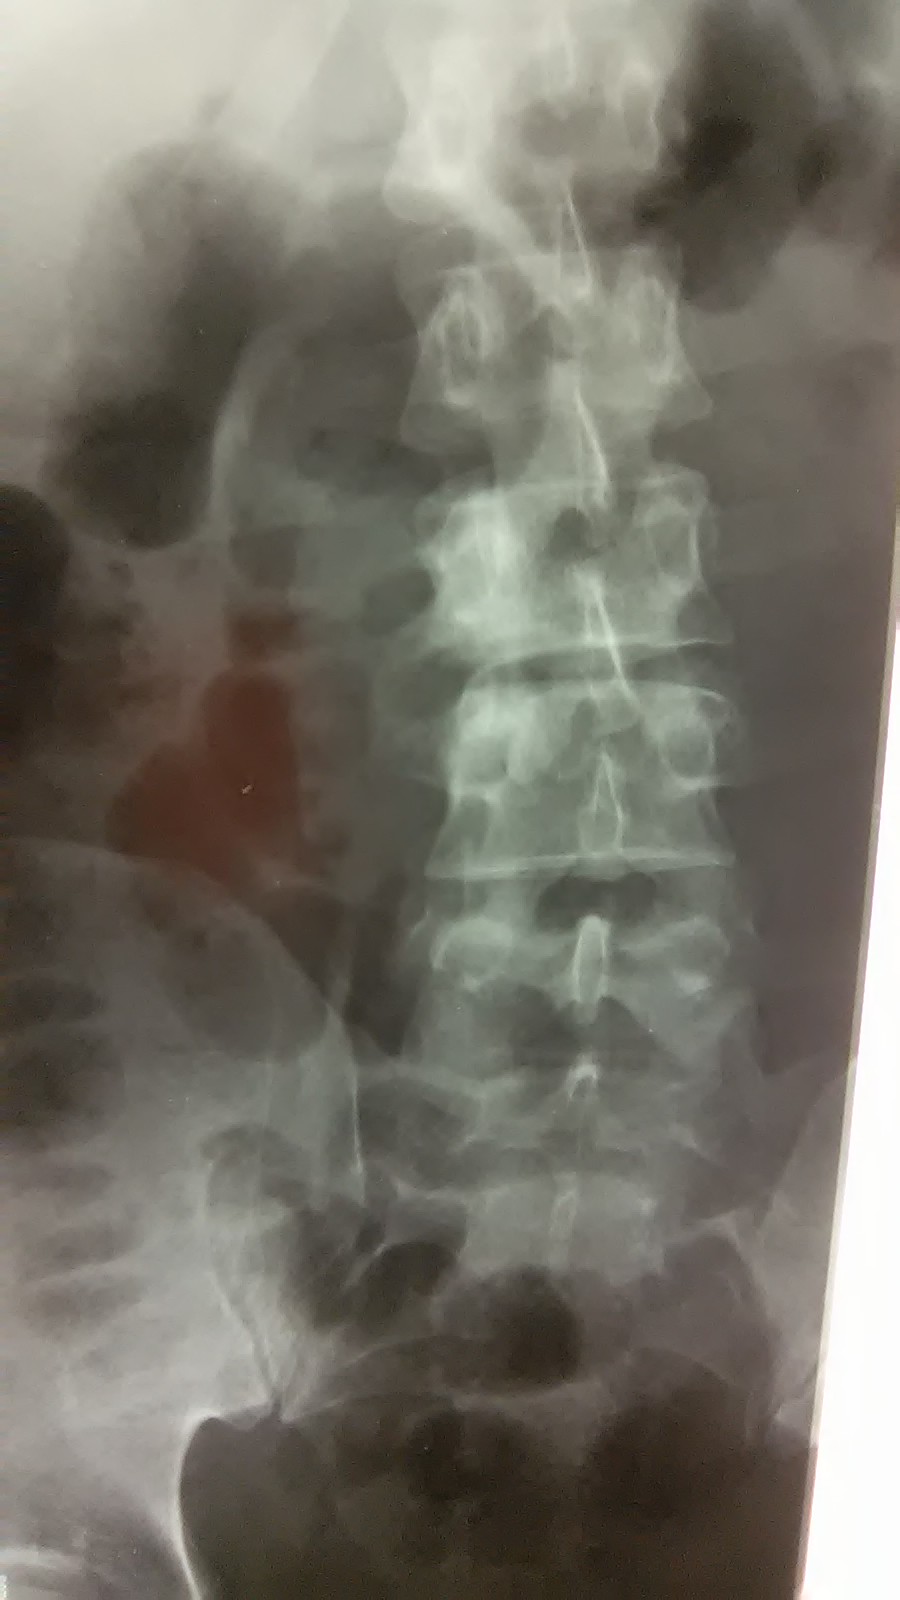

Хотел, видимо, с гнойником разобраться, но его не нашел. Что конкретно делал не знаю. Сегодня пациенту сделали Rtg.

Вложения

WP_20160627_002.jpg

WP_20160627_003.jpg

WP_20160627_004.jpg

Вот только добралась до истории болезни с описанием Rtg-снимков и заключением : "R-признаки спондилита на уровне L3-L4 с краевой деструкцией нижне-правого угла L3. Паравертебральный натечный абсцесс справа?".

Пациента записали на КТ.